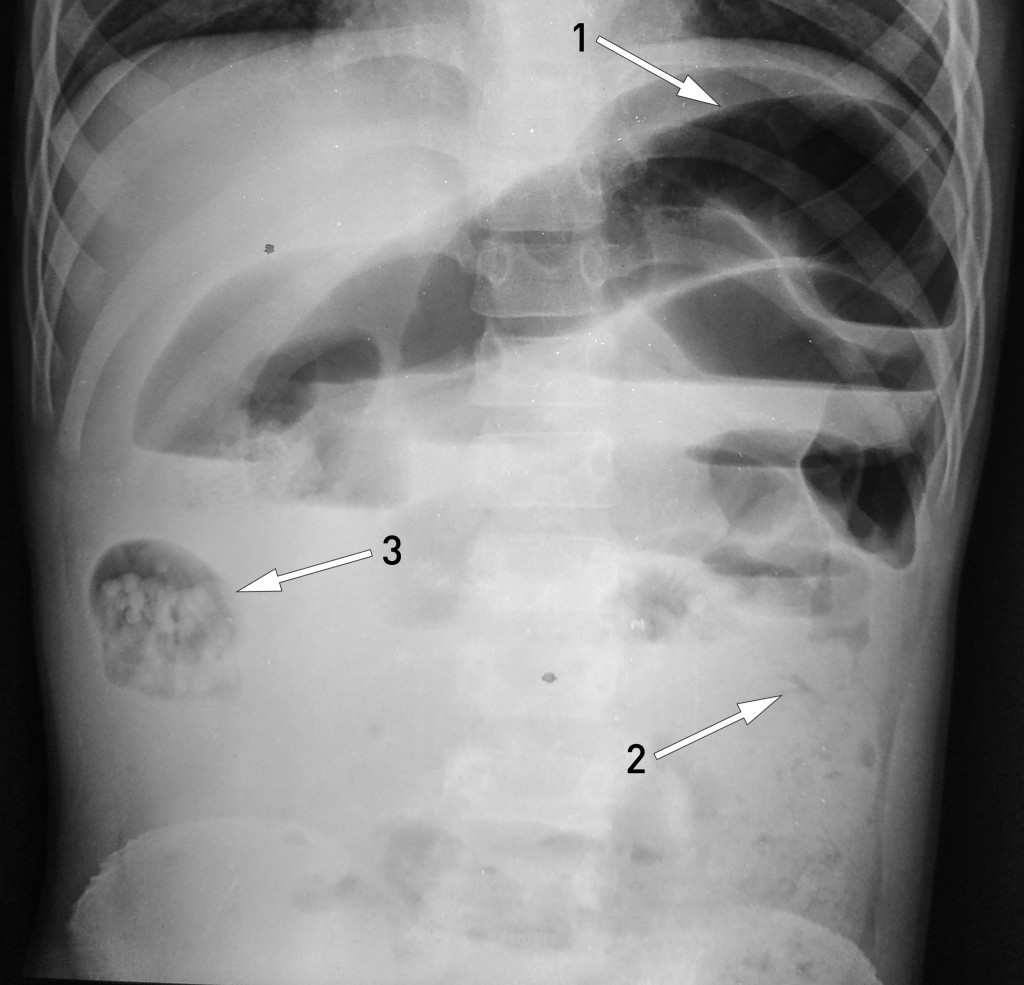

En ti år gammel gutt ble innlagt som øyeblikkelig hjelp på sykehus i et fattig område av Nepal. Han hadde betydelig forsinket lengdevekst. De siste tre dagene hadde han hatt magesmerter, oppkast og distendert abdomen. Han hadde ikke hatt avføring, men avgang av to levende spolormer per rectum. Stående røntgen oversikt abdomen (røntgenbilde) viste distenderte tynntarmsslynger (pil 1), men normal kolon (pil 2), altså funn forenelige med mekanisk tynntarmsobstruksjon. Man mistenkte at en ansamling av spolormer i et tarmsegment i høyre flanke (pil 3) – sannsynligvis i en tynntarmsslynge eller høyre hemikolon – hadde forårsaket en ileus.